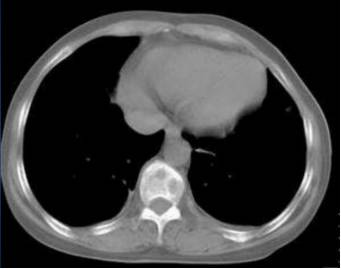

MM骨病变的检测手段主要包括X线、CT、MRI和PET/CT。X线的敏感性和特异性较低,目前已不作为MM影像检测的推荐。CT对脊柱、胸廓、骨盆的溶骨性病变的敏感性高于X线,能够更好的评估骨折风险和脊柱压缩性骨折的稳定性,CT在检测溶骨性病变方面比X线有更高的敏感性,但辐射较大。最近推出来的全身低剂量CT具有普通CT的高敏感性和特异性,且辐射较小,费用低,已逐渐成为患者的选择之一,但在国内该检测手段尚未广泛开展。

图2.CT显示MM患者脊柱的溶骨性病灶